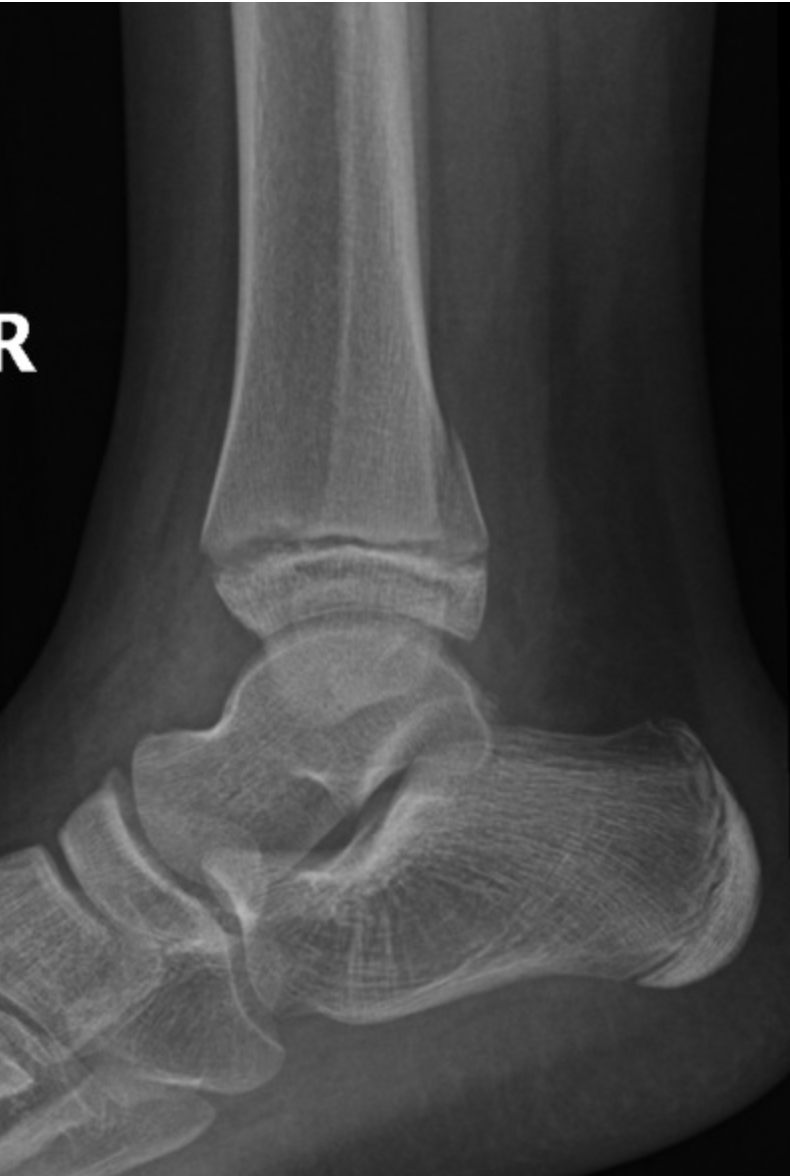

Q

ottowa ankle score

whether or not to x-ray